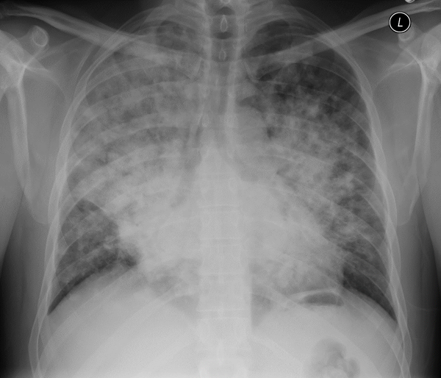

A 57 year-old man presents with pneumonia worsens despite treatment with empiric antibacterial antibiotics (ceftriaxone plus azithromycin). Bronchoscopy shows broad-based budding yeast. What is the likely cause of his pneumonia?

Blastomyces dermatitidis

Blastomyces = broad based budding yeast